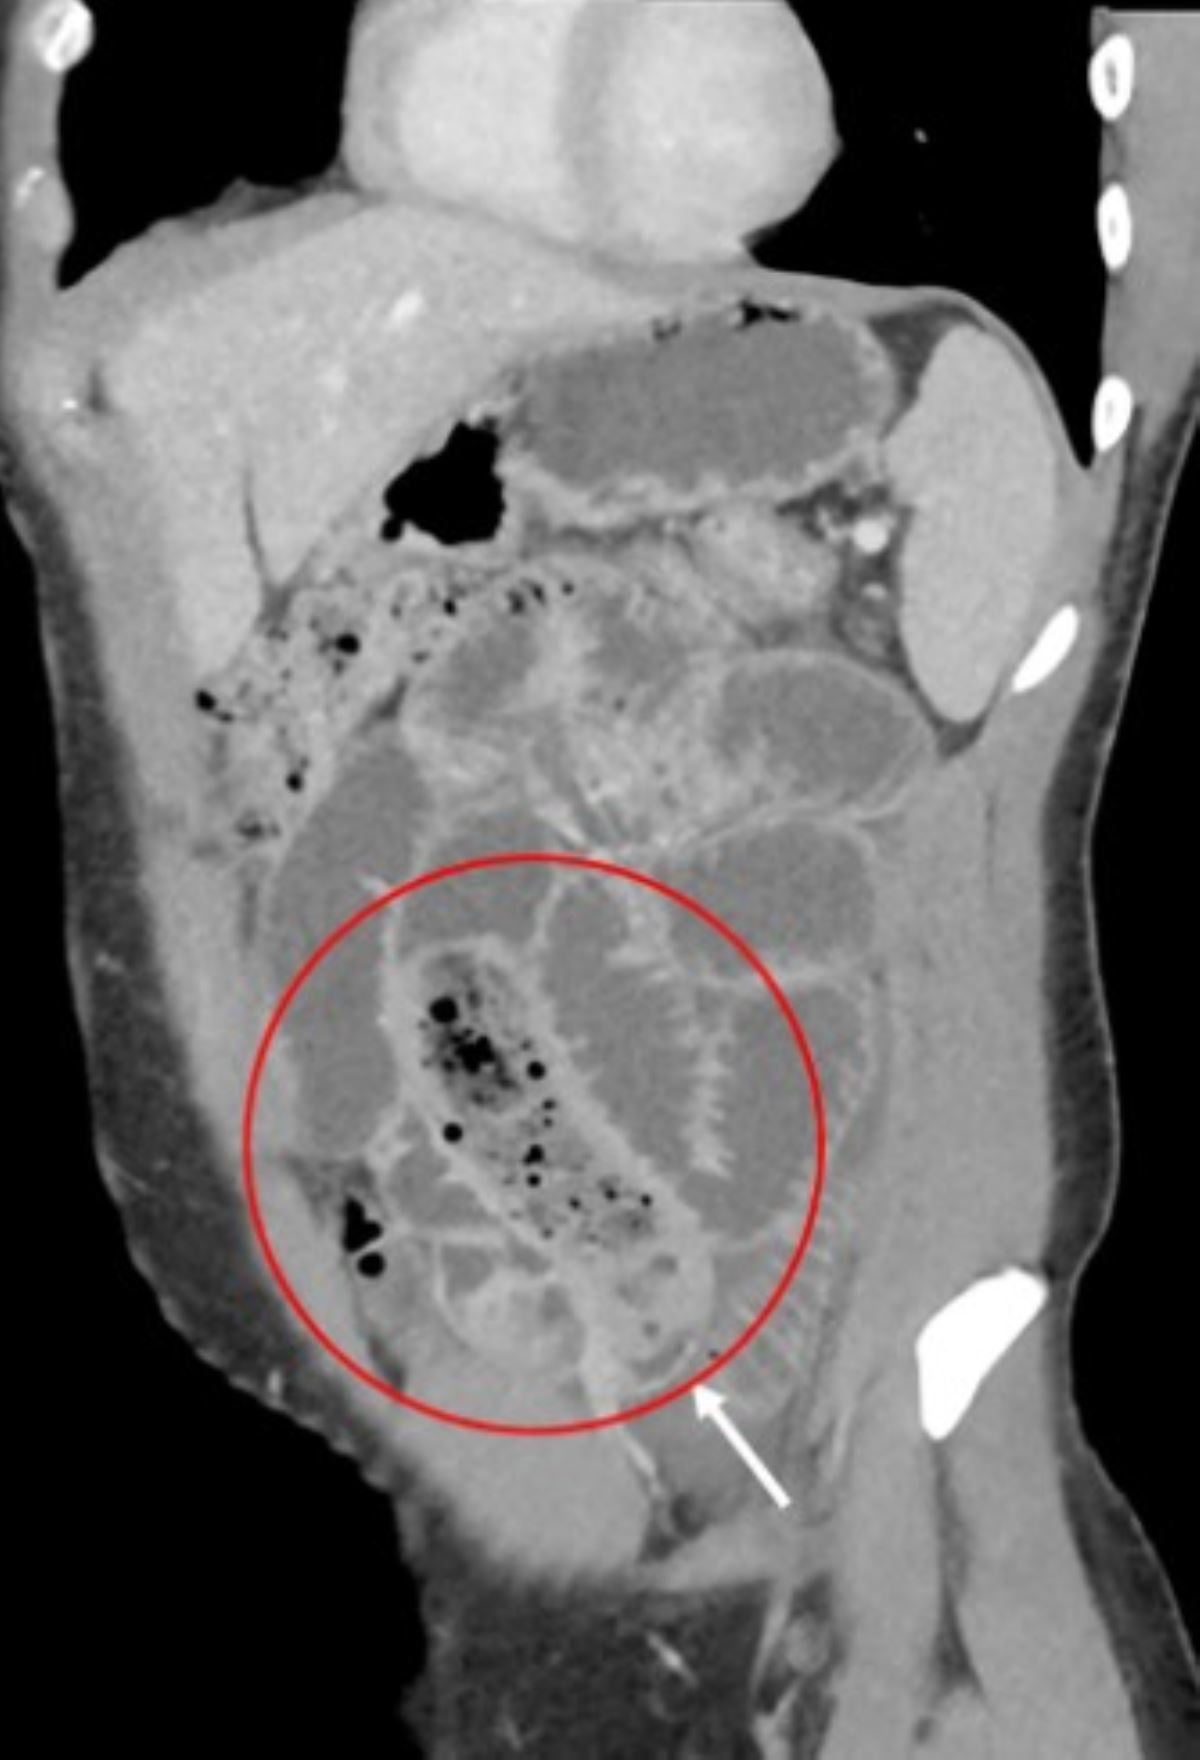

Doktorlar, tomografisi çekilen mide için cerrahi operasyon kararı aldı. Yapılan operasyon sonucunda adamın midesinden iki kat prezervatifin içine doldurulmuş muz çıkardı.